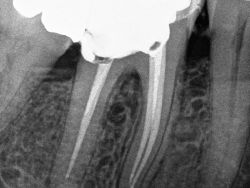

Endodontologie (Wurzelbehandlung)

Warum wird eine Wurzelkanalbehandlung notwendig.

Bei einer tiefen Karies oder wenn ein großeres Stück eines Zahns abgebrochen ist, können Bakterien bis in das Zahnmark vordringen und Entzündungen hervorrufen. Werden Warnhinweise wie Aufbiss oder starke Kälte- oder Wärmeempfindlichkeit nicht beachtet, schreiten die Entzündungen weiter fort. so dass irgendwann das Zahnmark abstirbt. Dringen die Bakterien noch weiter vor, entsteht an der Wurzelspitze eine Entzündung, die sogar den Kieferknochen auflösen kann.

Die moderne Wurzelbehandlung zeichnet sich im Gegensatz zur traditionellen manuellen Wurzelbehandlung durch den Einsatz von effizienten Instrumenten und Geräten aus. Dadurch erhöht sich die Qualität der Behandlung und die Erfolgsrate der Wurzelkanalbehandlung wird gesteigert.